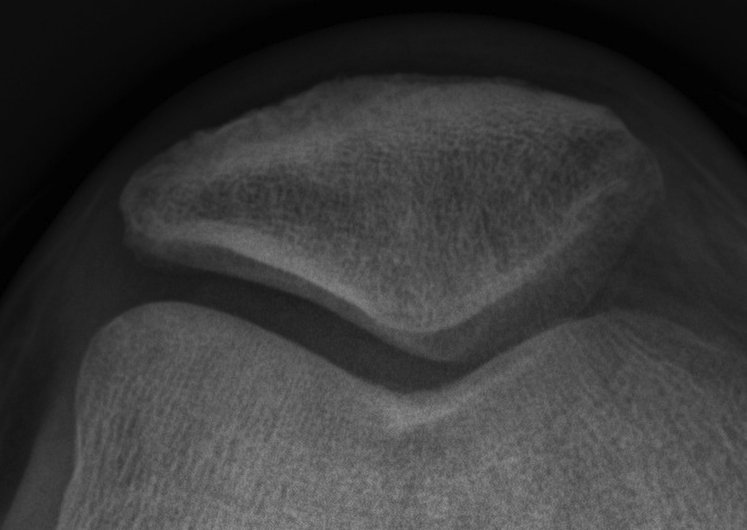

Patella Medial and Lateral Facets

Lateral surface larger than medial

- lateral cartilage thicker than medial

- medial & lateral separated by median ridge

Medial facet & odd facet are separated by another long ridge